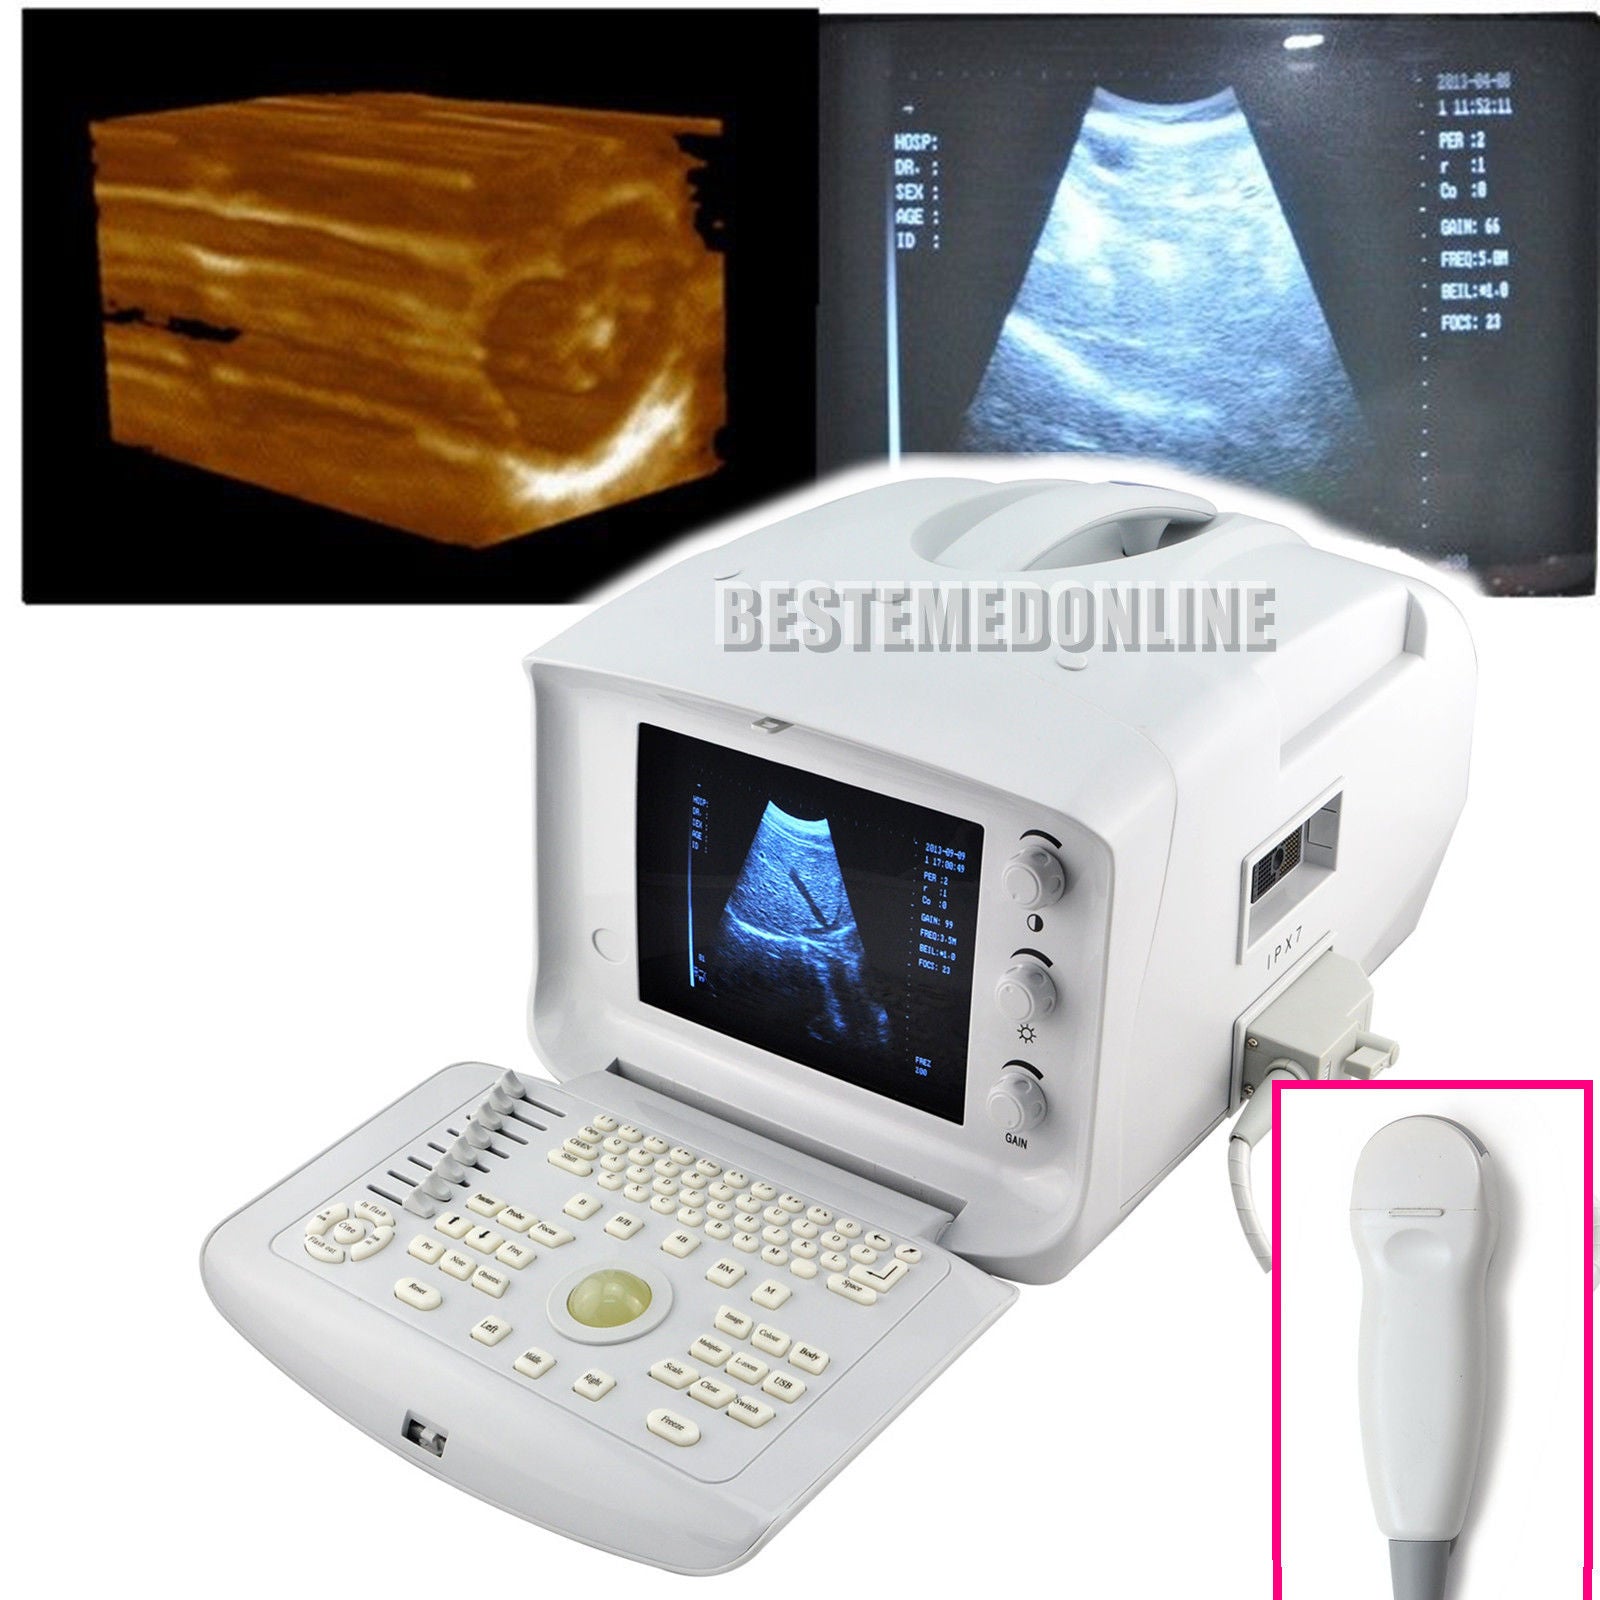

Ultrasound Scanner Machine 7.5Mhz Linear Probe Free 3D modul Vascular Scan Fast 190891351487

Ultrasound Scanner machine Rectal Probe 3D Laptop Machine Digital Veterinary AA 190891879431

Ultrasound Scanner Machine System Convex Linear Transvaginal 3 Probe 3D Software 190891518705

Ultrasound Scanner Machine Unit 3.5Mhz Convex Transvaginal Probe Free 3D CE

Ultrasound Scanner Machine with Micro-convex Transrectal Probe 3D Good Image 190891875310

Ultrasound Scanner Micro-Convex Probe Ultrasonic Machine 3D Ultrasound Unit